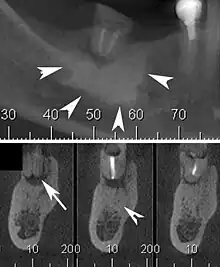

| Cone beam CT scan presenting a diffuse hyperdense lesion in the apex of a mandibular molar (arrowhead, top) adjacent to an inflammatory periapical lesion (arrow, bottom).[1] | |